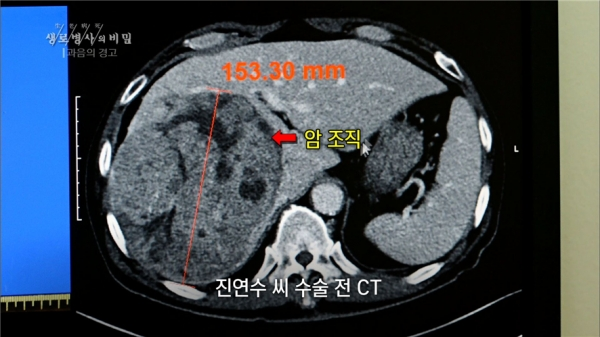

우선, 간은 알코올을 분해하는 데 가장 중요한 장기인 만큼, 알코올에 의한 손상도 그만큼 심하게 받는다. 이날 ‘생로병사의 비밀’에서는 수십년 간 과음으로 인해 간 수치가 이상해 검사를 받은 결과 간암 판장을 받은 사례와, 과거의 음주력으로 인해 간경화 증세를 동반한 초기 간암을 진단 받은 사례를 소개한다.